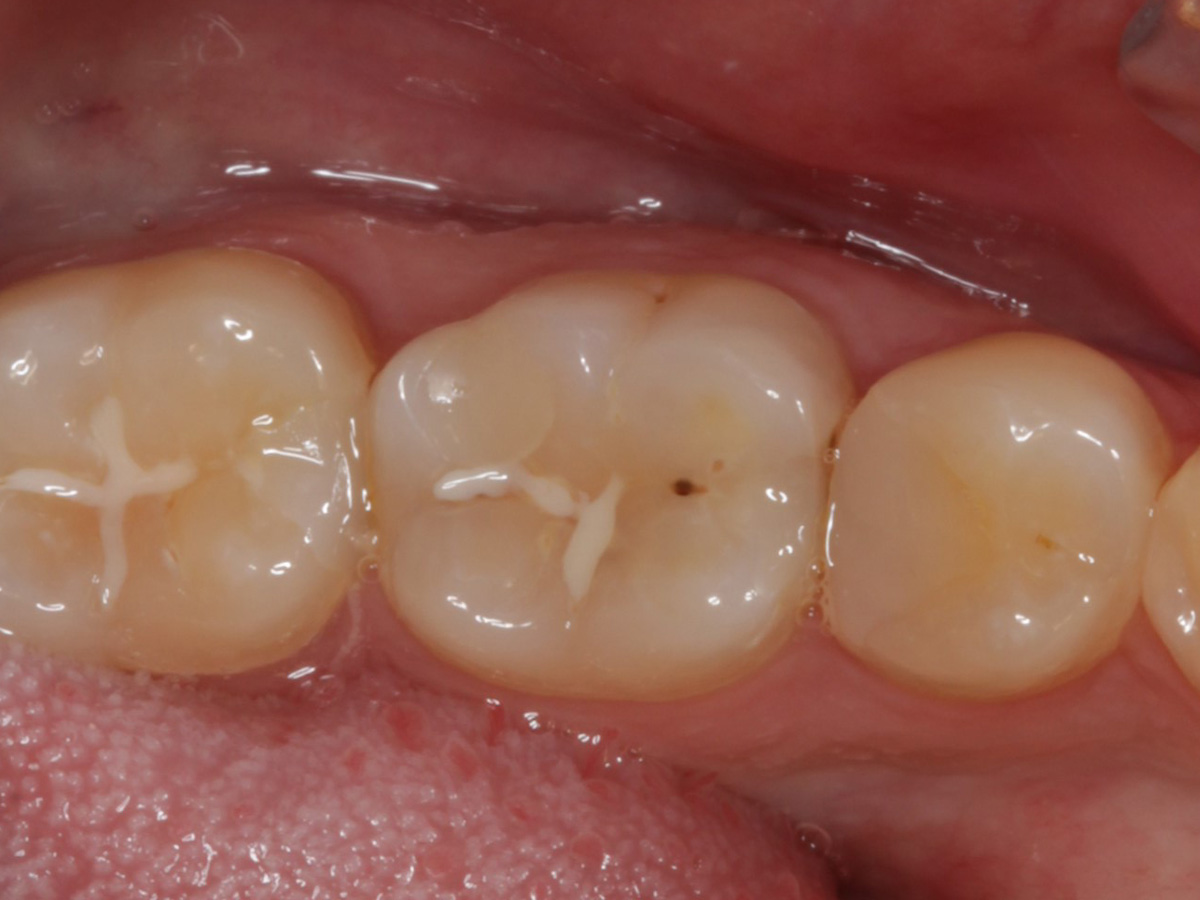

Kavitäten gefüllt (Injektion Moulding: Flowkomposit, erwärmtes Seitenzahnkomposit aus Karpule)

Abbildung 20

Abbildung 21

Zahnseidenkontrolle: kein Überschuss, satte Kontaktpunkte